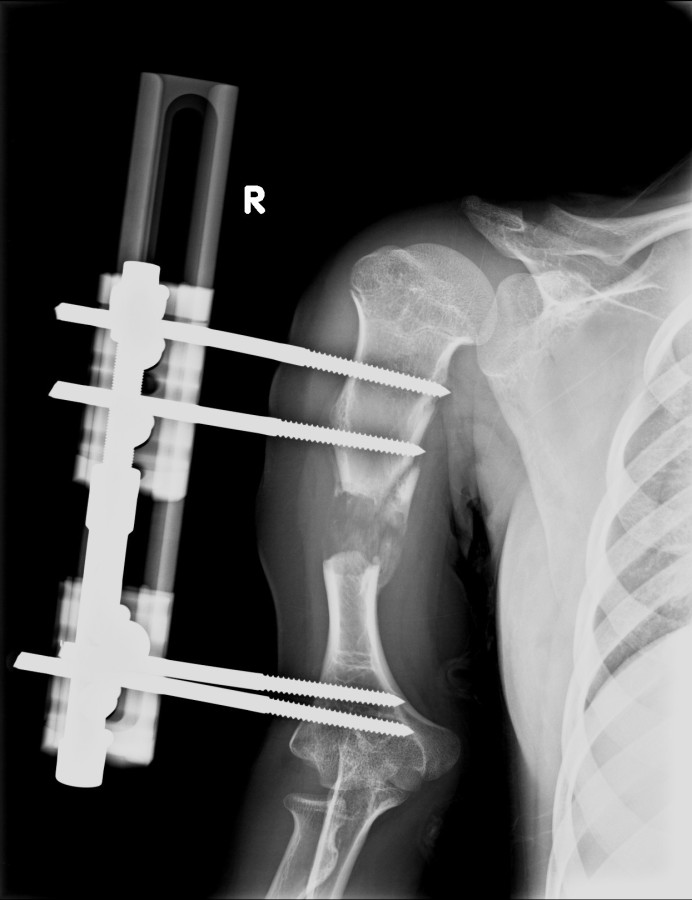

13-15 yaşlar arasında Her iki humerusu (kol) 8-12 cm boy uzatma Dirseklerin fleksiyon deformitesini düzeltme Ortalama eksternal fiksasyon tedavi süresi = 6-8 ay Alt uzuvların iki uzatması arasında üst uzuvlar uzatılarak alt uzuvların dinlenmesi sağlanmış olur. Cihaz çıkartıldıktan sonra en erken ikinci uzatmaya başlama süresi 6 aydır. Bilateral femoral uzatmalarda uzatma fazı sırasında hastanın yürümesi mümkün değildir. Ayakta durmaya sadece hasta transferi sırasında izin verilir. Uzatma fazında ambulasyona sadece tekerlekli sandalye ile izin verilir. Konsolidasyon fazında ise tedrici olarak daha fazla yük verilmesine ve cihazın çıkmasına yakın serbest yürümeye izin verilir. Bilateral tibial uzatmalarda ilk günden itibaren yürüteç veya koltuk değneği ile hastanın yük vermesine izin verilir. Uzun gezintiler tekerlekli sandalye ile yapılmalıdır. Bilateral humeral uzatmalarda hemen hemen hiçbir aktivite kısıtlaması yoktur. Uzatma süresince her iki haftada bir yapılan takiplerde kantitatif duyusal sinir testleri doktor tarafından yapılmalıdır. Bu gelişmekte olan sinir sorunlarını klinik olarak ortaya çıkmadan yakalamaya izin verir. Femoral ve humeral uzatmalarda çok nadir görülmesine rağmen tedavi edilmedikleri durumda düşük ayağa (ayağı yukarı çeken kasları innerve eden sinirin felci) neden olabilirler. Eğer erken tespit edilir ve uzatmanın hızı azaltılırsa, sinir problemi genellikle kendiliğinden düzelir ve uzatmaya düşük hızda devam edilir. Uzatmada yavaşlamaya rağmen sinir problemi devam ederse sinirin cerrahi olarak gevşetilmesi gerekir. Bu işlem 1cm’ lik bir kesi ile yapılabilen ve hastanede bir gece kalmayı gerektiren küçük bir işlemdir. Bu ameliyat el bileğinde sinir sıkışması (karpal tünel sendromu) için yapılana benzerdir.